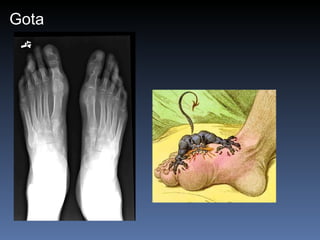

Gota Asimetrica Mas comun en la 1a.  articulacion M.T.T.F. Es comun la bursitis del olecranon Erosiones con bordes sobresalientes (mordedura de rata) Edema de partes blandas Depositos con densidad de tejidos blandos (tofos)

Gota